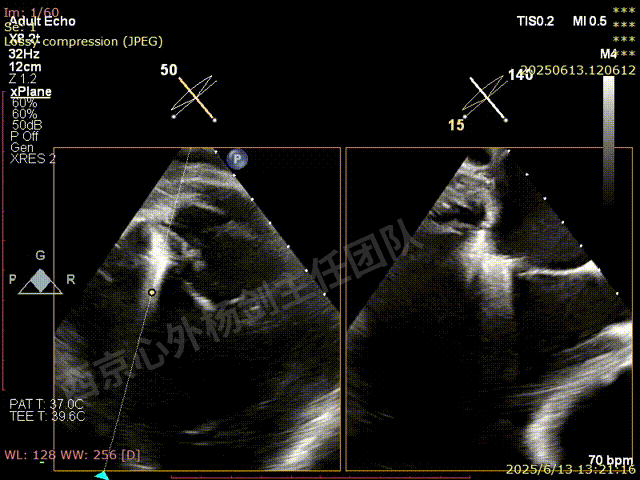

TAVR术后,全心增大,二尖瓣反流重度,三尖瓣反流重度。中量心包积液。左室严重增大,标准图像调整困难。主动脉瓣位带支架人工瓣膜瓣叶启闭正常,主动脉瓣位人工瓣上血流速度Vmax 148cm/s,PGmax 9mmHg,Vmean 86cm/s,PGmean 2mmHg, VTI 34.7cm,瓣周反流(轻)。估测肺动脉收缩压约49mmHg;左室收缩功能明显减低。LVEF:23%,EDV:364ml,ESV:221ml。

彩色血流示:二尖瓣反流缩流颈彩宽6.6mm,面积17cm²,容积30ml;二尖瓣瓣口面积6.6cm²,瓣环内径:左右径34mm,前后径34mm。2区瓣叶长度:前叶36mm,后叶20mm,叶环比1.6. 三尖反流面积17.2cm²,容积33ml,Vmax 291cm/s,PGmax 34mmHg。

TEER术前超声评估

二尖瓣后叶栓系严重,前叶相对错位,反流束沿2区分布广泛,2偏3区处存在反流。

反流宽度至少23mm,因影像调整困难,考虑实际反流更宽。